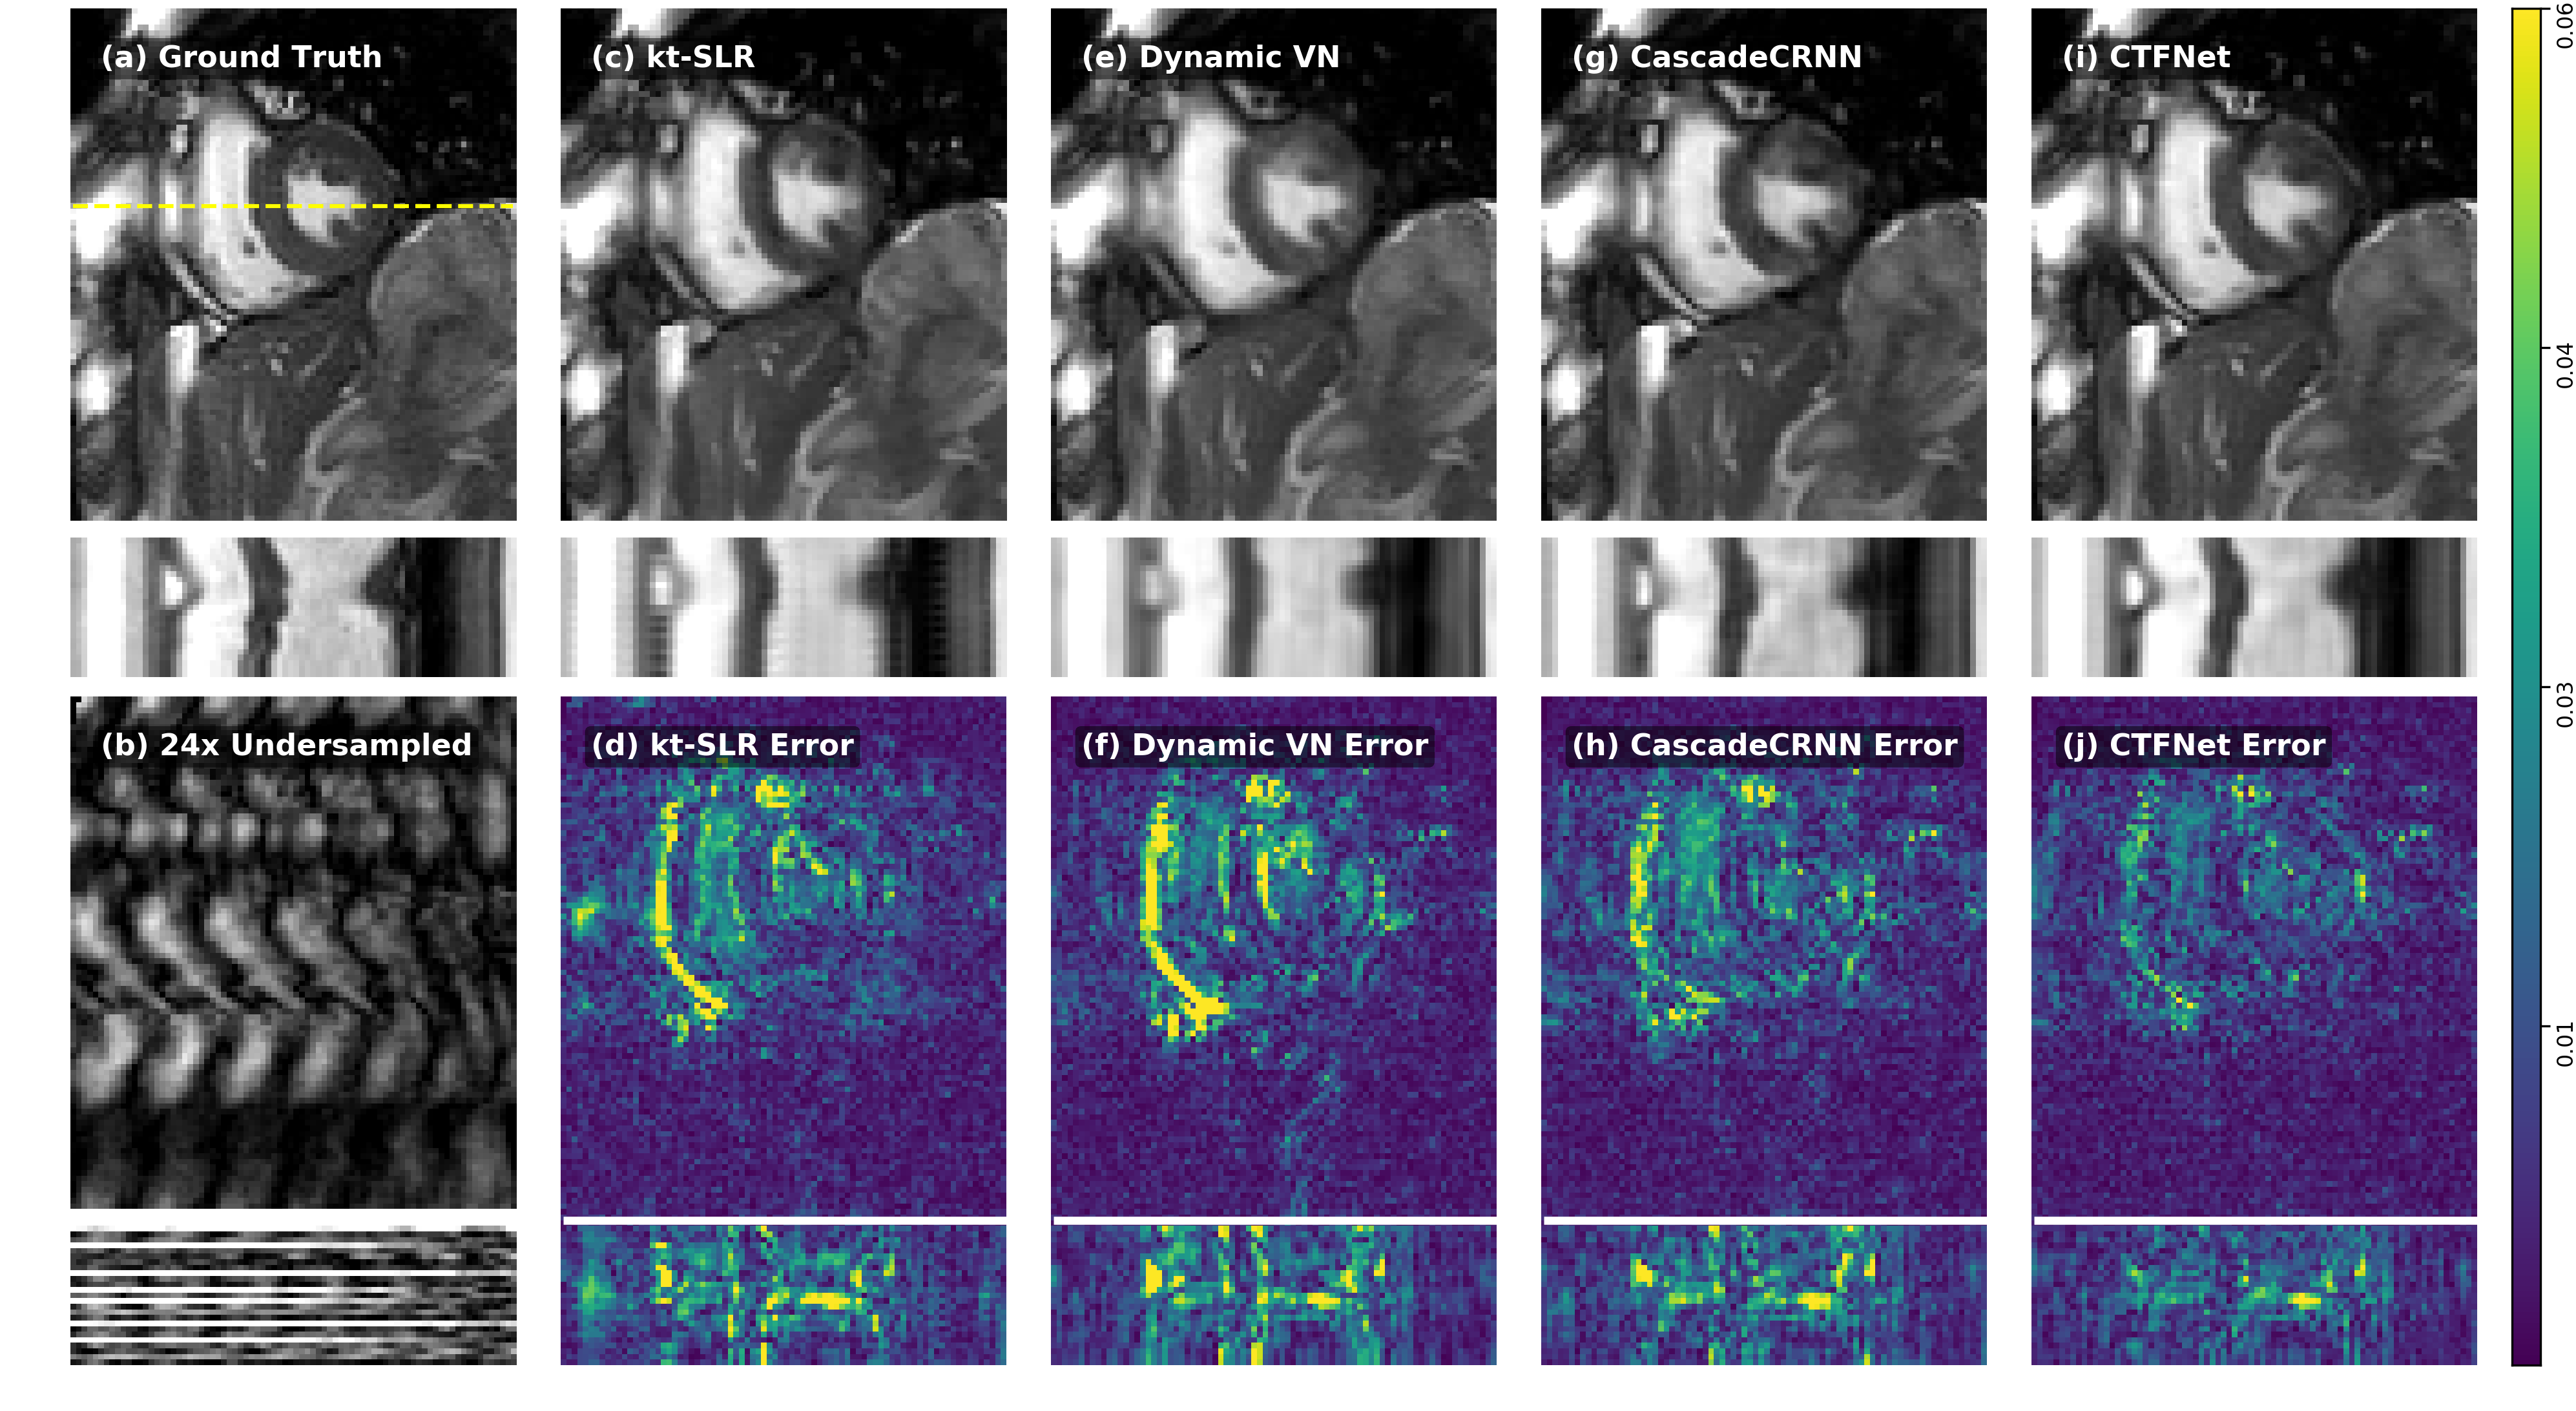

Quantitative comparison results of different methods on dynamic multi-coil cardiac data with various high acceleration rates (, and ) are presented in Table 1. The results reported were on the entire 228 2D+t slices on Dataset A. It can be seen that our proposed CTFNet outperforms - SLR by a large margin in terms of all these measures at different undersampling rates. It also offers a much faster (1000) reconstruction speed with 2.8s for the entire sequence of one slice compared with - SLR with 2444.8s for the same reconstruction. In comparison to other DL-based methods which have been carefully enhanced to incorporate temporal information, our proposed approach can still achieve better performance on all acceleration rates, with an improvement of around 1dB PSNR and 1.5% SSIM increase over the most competing method (CascadeCRNN). The performance gap of the improvement is also increasing as acceleration rate increases. All results were statistically significant with . Additionally, we also compared the qualitative results on and undersampled data (equivalent scan time: 15s and 10s respectively within a single breath-hold) in Fig. 3 and Supporting Information Fig. S2, which shows the reconstructed images along both spatial and temporal dimensions as well as their corresponding error maps on a patient and a healthy subject. Compared to other competing methods, it can be observed that our proposed model can faithfully recover the images with smaller errors especially around dynamic regions, and can also produce sharper reconstructions along temporal profiles.

We compared our proposed approach (CTFNet) with representative MR reconstruction methods, including state-of-the-art CS and low-rank based method - SLR [7], and two variants of DL methods, dynamic VN [33] and Cascade CNN [27, 24], which have been substantially enhanced to adapt to dynamic parallel image reconstruction. Dynamic VN [33] learns the complex spatio-temporal convolutions in contrast to the original VN [19], and for strong comparisons with our method, we propose to improve it by incorporating the temporal average baseline as an initialisation. Similarly, as to Cascade CNN with the D-POCSENSE framework [24] originally designed for static PI, we also refined it to learn the residual of the temporal average, and adjusted it with the same convolutional recurrent architecture as CTFNet to equip it with the ability to exploit spatio-temporal correlations. Thus we term it as CascadeCRNN. The network architecture for CascadeCRNN was the same as -CRNN and the number of iteration steps was set to 5 for all DL methods. - SLR formulation has also been extended to be used with multi-coil data based on SENSE model in contrast to its original implementation [7].